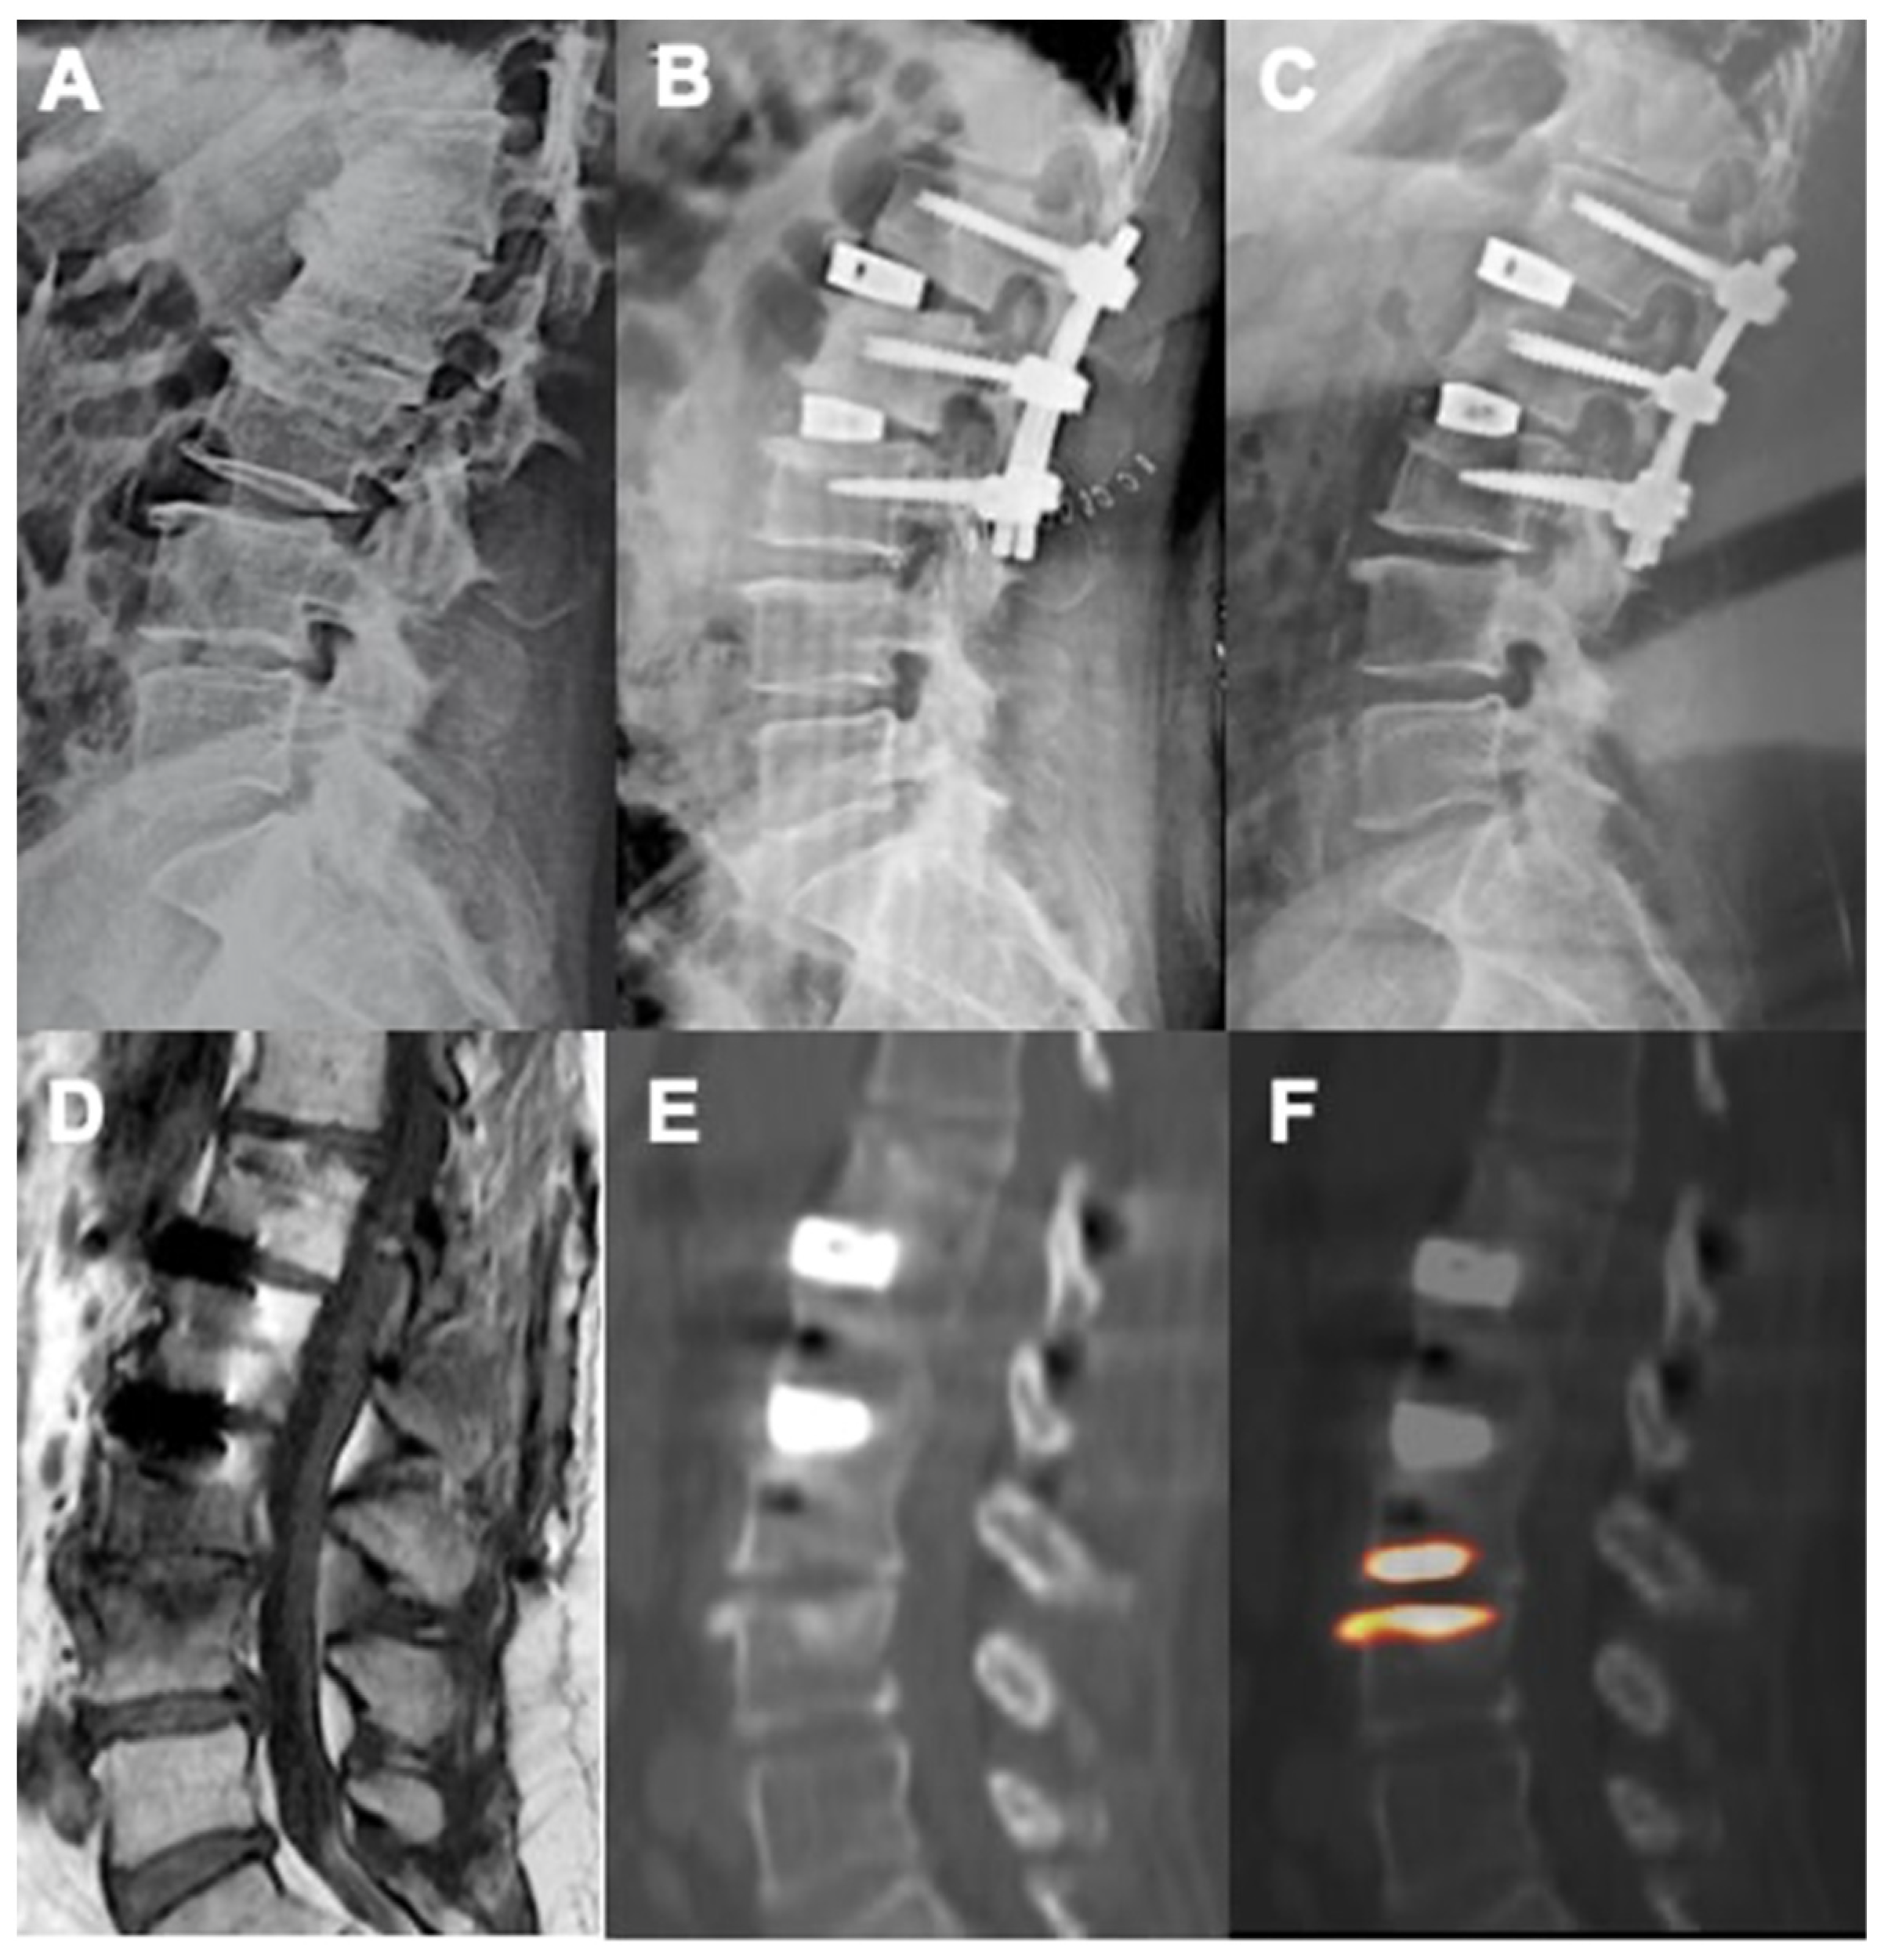

Figure 5.

Pre-operative standing X-ray (A), immediate postoperative (B), and 58 weeks follow-up (C) showing good sagittal correction after L1-L2 and L2-L3 XLIF surgery. PET (F) and CT (E) images showed no activity at the level of the implanted vertebral plates suggesting a proper integration with the bone. Appearance of L3-L4 activity was related to the occurrence of degenerative junctional pathology as also shown by T1-weighted MRI sequences with Modic I signal (D).

According to our results, tracer uptake was already visible in the first week after implantation. This first finding is probably related to the increase in blood flow after preparation of the vertebral endplate and to the consequent bone-cell activation at the contact surface. Therefore the metabolic activity, probably linked to the osteogenic activity, increases progressively until reaching a peak between approximately the 3rd and 4th month after surgery (Figure 2 and Figure 3). This progressive increase in activity can be correlated, as supported by in vitro studies, to the migration, adhesion, and growth of cells from the vertebral bone tissue and to consequent osteoblastic activity with apposition of the bone matrix within the cage pores [34]. In the later stages, the metabolic hyperactivity on the vertebral endplates decreases progressively and tends to disappears around the 10th–12th month after surgery (Figure 2 and Figure 3). This reduction may be the expression of a lower need for bone remodeling caused by sufficient acquired interbody fusion and stability [35,36]. The reparative phase could tend to run out after the formation of bone bridges between the cages and the vertebral plate. The growth of tissue inside the cage can be the basis for a real osteo-integration avoiding delayed subsidence and ensuring stability of the obtained correction.

Among future perspectives, other than its already-described role in diagnosing symptomatic subsidence and implant failure or loosening, the use of 18F-NaF PET/CT could be of importance in the correct clinical diagnosis of adjacent-segment disease and especially in identifying symptomatic discs in the context of a multilevel degenerated spine, playing the part of the outdated spinal discography (Figure 5).